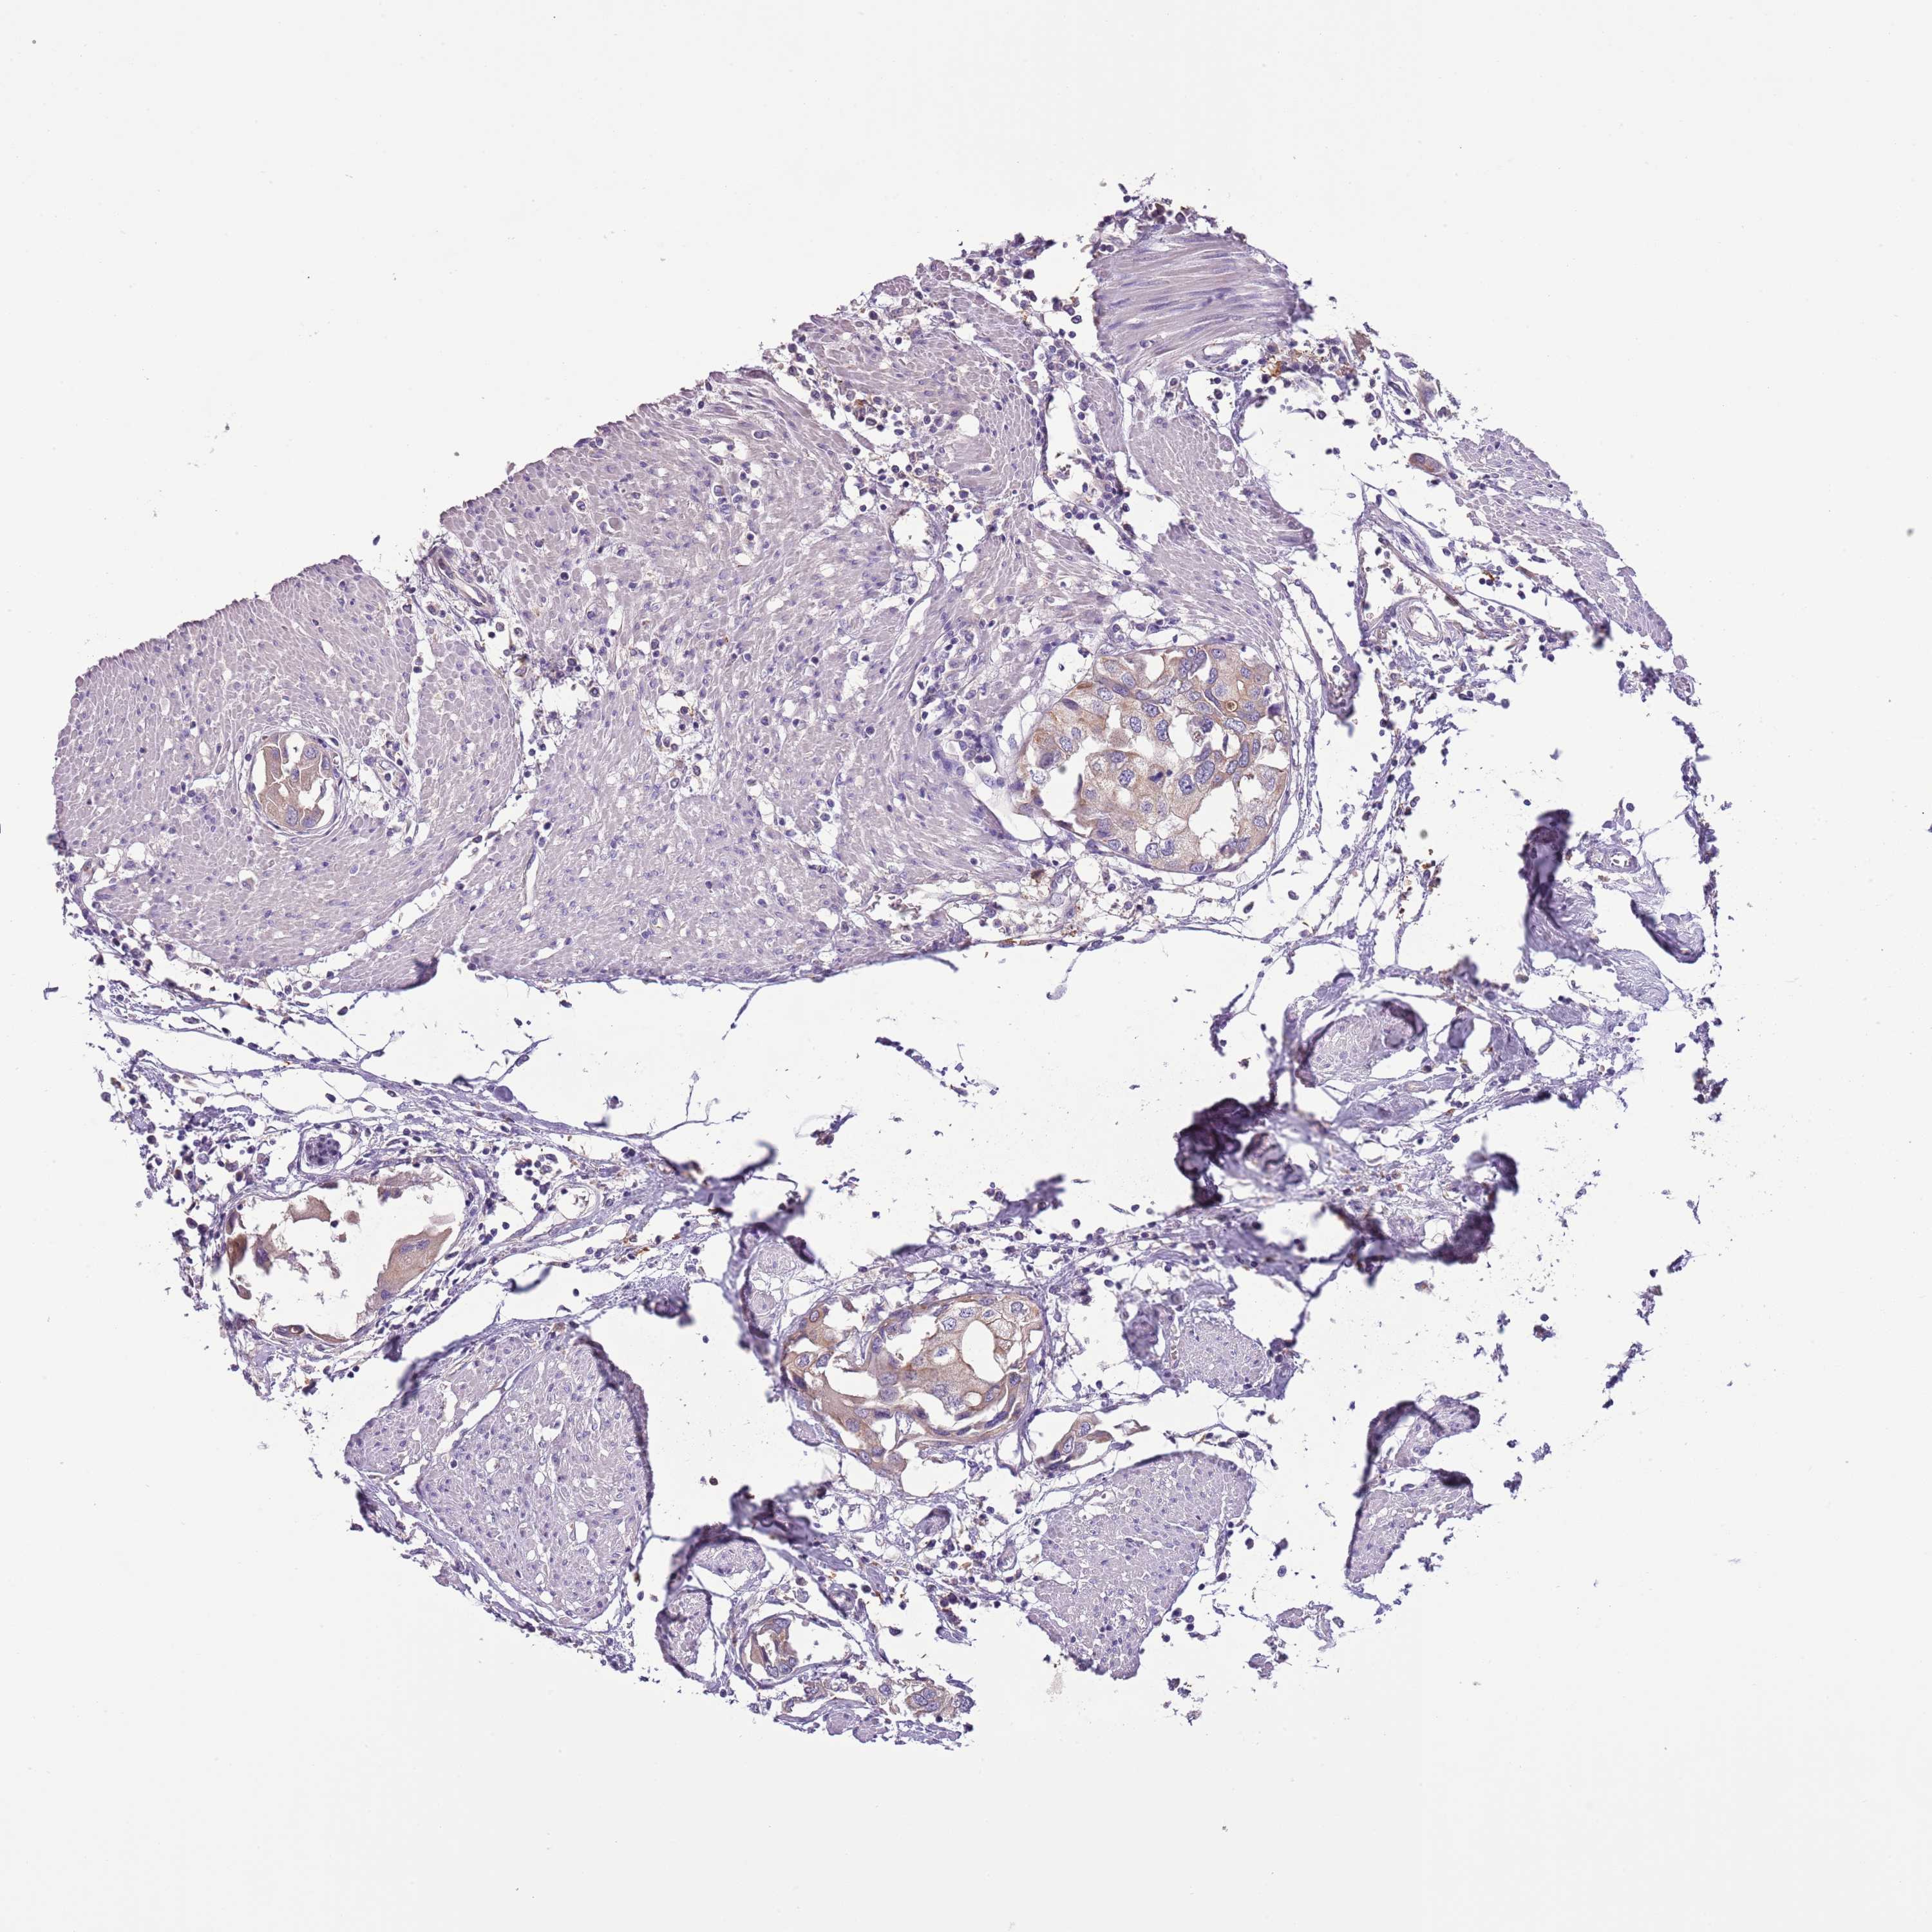

UROTHELIAL CANCER - Protein expressioni

A mouse-over function shows sample information and annotation data. Click on an image to view it in a full screen mode. Samples can be filtered based on level of antibody staining by selecting one or several of the following categories: high, medium, low and not detected. The assay and annotation is described here.

Note that samples used for immunohistochemistry by the Human Protein Atlas do not correspond to samples in the TCGA dataset.

Antibody stainingi

Antibody staining in the annotated cell types in the current human tissue is reported as not detected, low, medium, or high, based on conventional immunohistochemistry profiling in selected tissues. This score is based on the combination of the staining intensity and fraction of stained cells.

Each image is clickable and will lead to virtual microscopy that enables deeper exploration of all samples and also displays staining intensity scores, fraction scores and subcellular localization as well as patient and tissue information for each sample.

Antibody HPA047927

Staining

High

Medium

Low

Not detected

Intensity

Strong

Moderate

Weak

Negative

Quantity

>75%

75%-25%

<25%

None

Location

Nuclear

Cytoplasmic/membranous

Cytoplasmic/membranous,nuclear

Urothelial carcinoma, High grade

Urothelial carcinoma, Low grade

Urothelial carcinoma, NOS